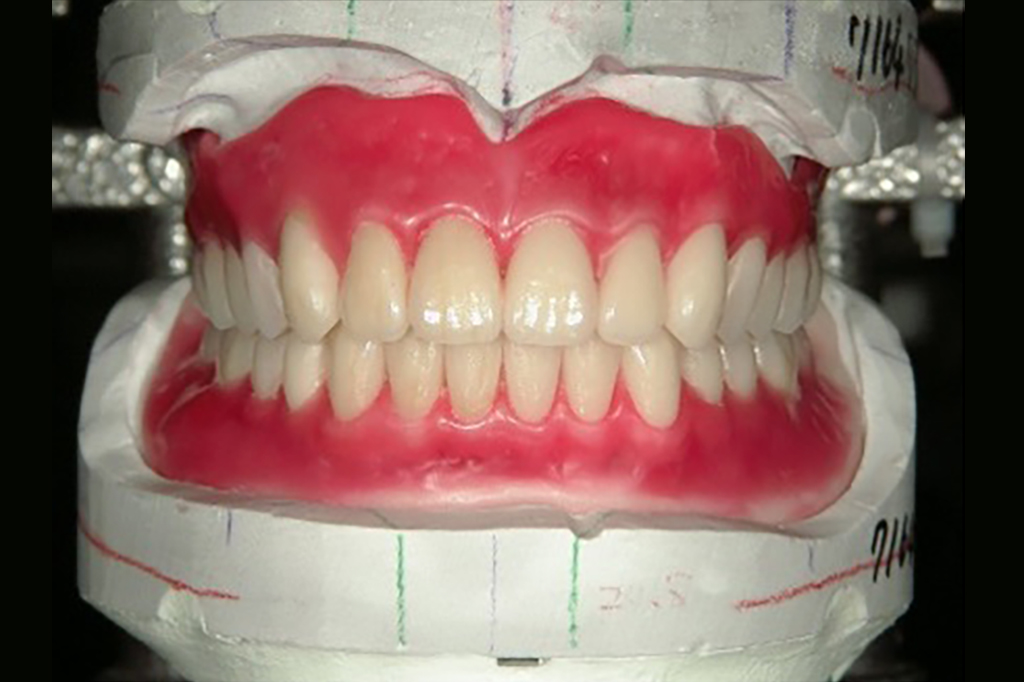

かみ合わせの調整

• 兵庫県南あわじ市・医療法人 太田歯科・矯正歯科

上下のアゴのかみ合わせを記録した後は、しっかり咀嚼ができるよう人工の歯を並べます。歯の見え方、歯の角度、歯の色などにも注意して作製します。